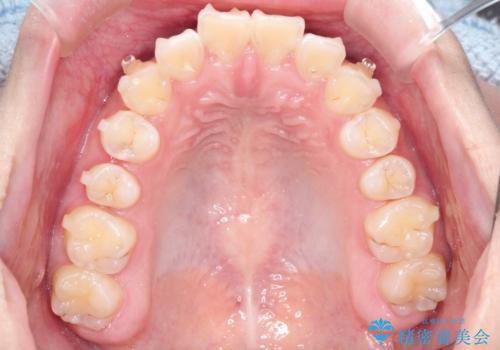

インビザラインによる出っ歯の非抜歯矯正

- 前歯が出ているのを主訴に来院されました。

上の前歯が前方に傾斜しており、上の前歯と下の前歯が接触していない状態でした。

上の奥歯を後方に移動させて、前歯を引っ込める計画としました。

しっかり使っていただけたので、スムーズに治療を終了することができました。